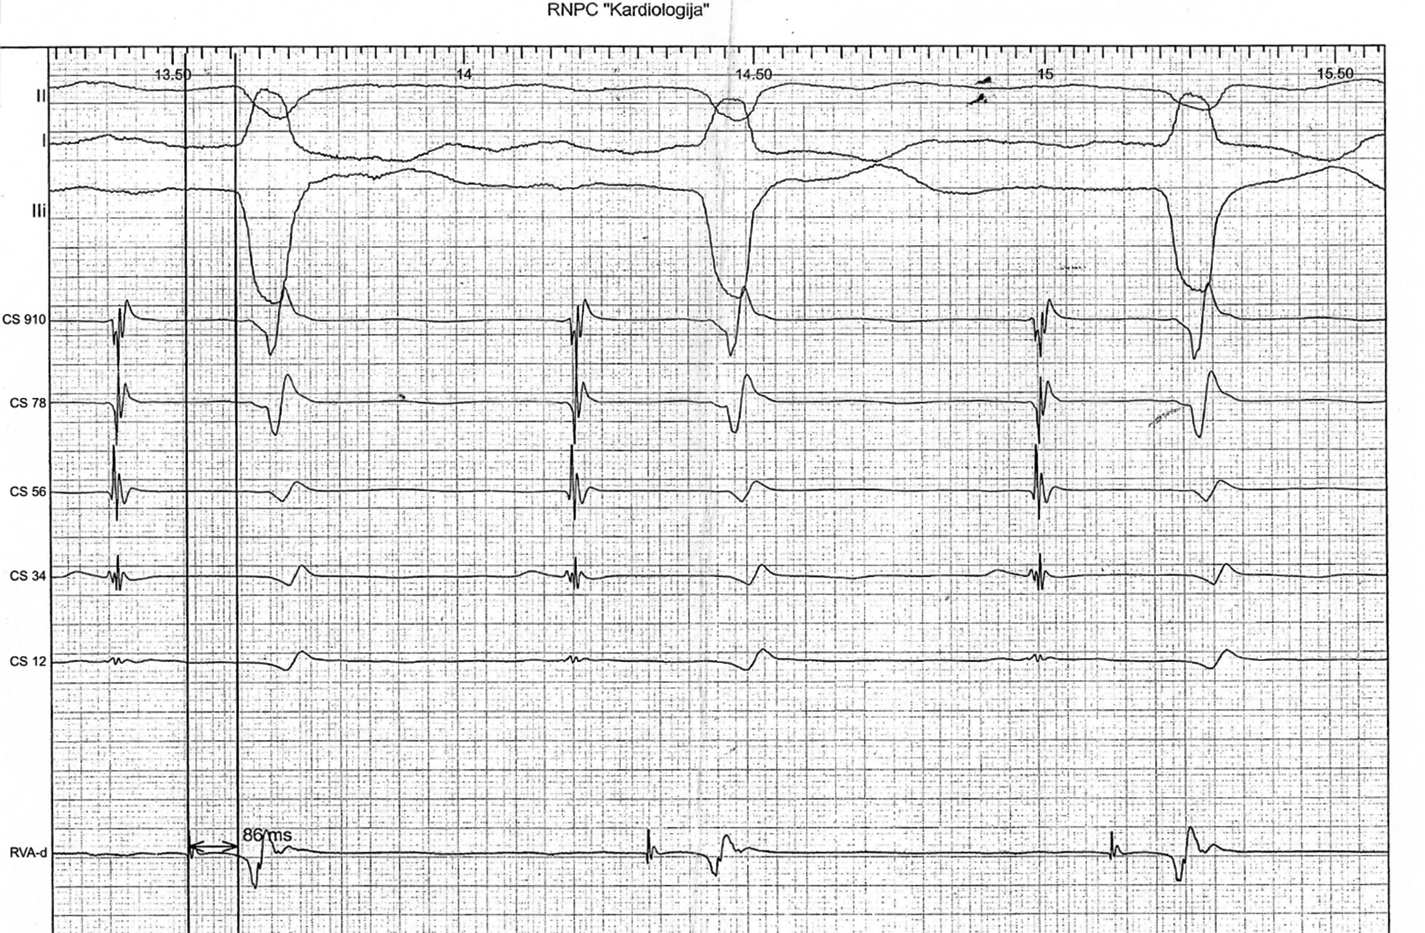

Принимая во внимание клиническую картину заболевания, результаты лабораторно-инструментальных исследований, пациентку повторно госпитализировали в кардиологическое отделение в сентябре 2024 г. для выполнения ЭЭФИ и определения дальнейшей тактики ведения. По данным ЭхоКГ, определена ФВ ЛЖ 56%, гипокинез базального передне-перегородочного и базального перегородочного сегментов ЛЖ; полости сердца не расширены. При выполнении 2D-Strain ЭхоКГ не выявлено снижения глобальной продольной деформации ЛЖ (GLS — –20,0%) (риc. 4). По данным ЭЭФИ, зафиксировано удлинение интервала HV — 86 мс (рис. 5).

Рис. 5. Эндокардиальное электрофизиологическое исследование пациентки К. Удлинение интервала HV — 86 мс.